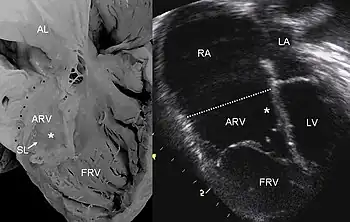

| Echocardiogram showing typical findings in severe tricuspid regurgitation | |

Definitive diagnosis is made by echocardiogram, which is capable of measuring both the presence and the severity of the TR, as well as right ventricular dimensions and systolic pressures.[12] Cardiac MRI or CT scan may also aid in the diagnosis of TR.[3] On imaging studies, a regurgitant volume greater than 45 milliliters or greater than 50% regurgitation across the tricuspid valve is associated with poor outcomes.[3]